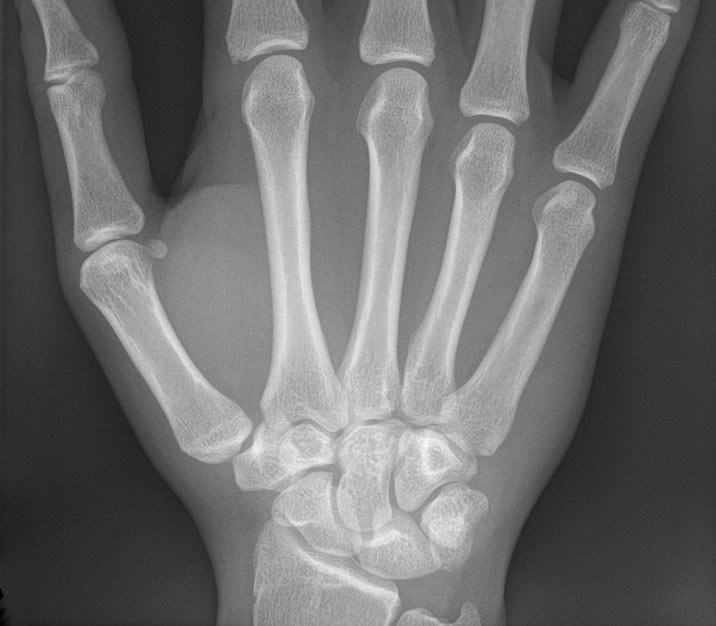

A Coast Guard Air Station Kodiak MH-60 Jayhawk helicopter crew medevaced a 58-year-old male after he suffered an ankle injury while aboard the F/V NEW DAWN. The 50-foot commercial vessel was near Shelikof Strait when the incident occurred on Sunday, June 18th.

“Due to the crewman’s possible need for an orthopedic surgeon, we determined the best course of action was to get him off the New Dawn and place him aboard the Jayhawk helicopter for transfer to advanced medical care” said Mr. Cory Cichoracki, watchstander at Sector Anchorage command center. “Despite the weather, the aircrew alongside the crew of the New Dawn, was able to complete a successful hoist.”